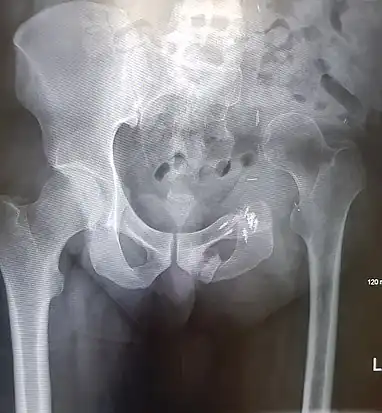

An x-ray of the same pelvis taken eighteen months after surgery highlighting the femur migration to its final resting place.